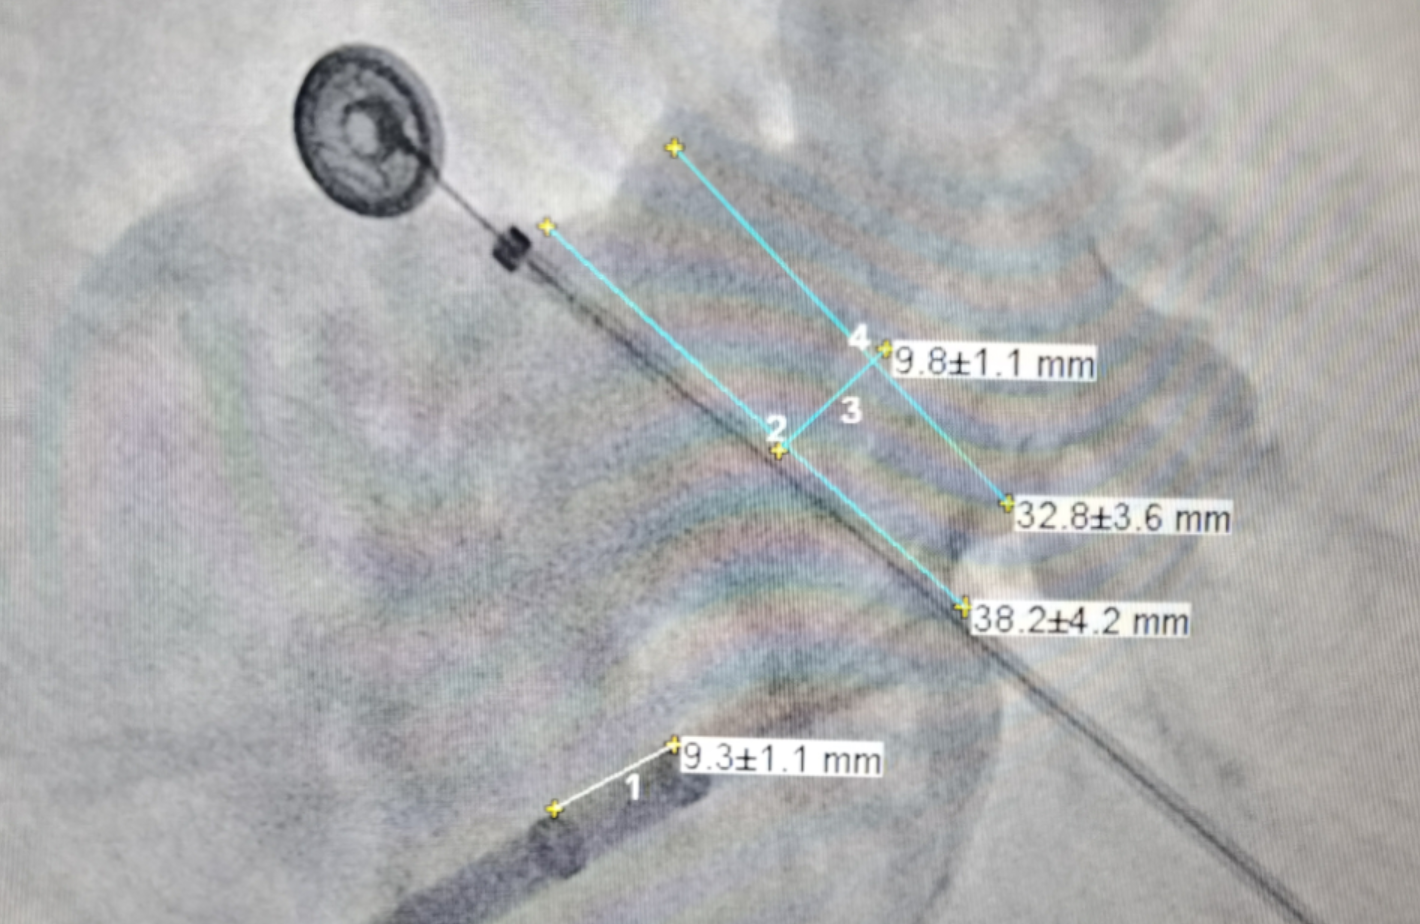

DSA下显示敞口超大菜花型心耳